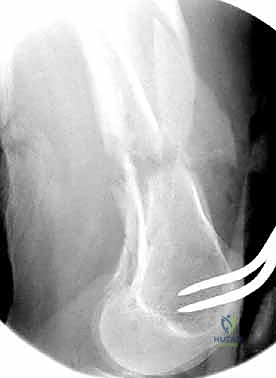

- الأشعة السينية (X-Rays): أخذ صور من زوايا متعددة (أمامي خلفي، وجانبي) لتحديد موقع الكسر ونوعه.

- الأشعة المقطعية (CT Scan): وهي ضرورية جداً في كسور عظم الفخذ البعيدة، خاصة إذا كان الكسر يمتد إلى داخل مفصل الركبة (Intra-articular fractures). تساعد الأشعة المقطعية الدكتور هطيف على بناء نموذج ثلاثي الأبعاد للكسر، مما يسهل التخطيط الجراحي وتحديد أماكن وضع المسامير بدقة.